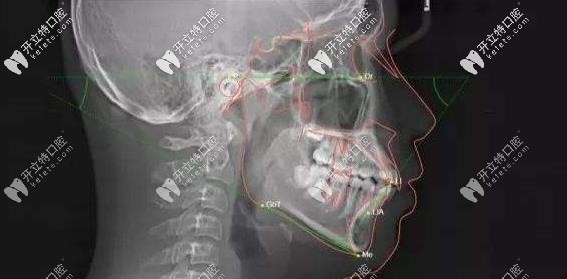

怎么辦!感覺(jué)這次活動(dòng)超級(jí)劃算啊有木有!圣貝口腔還為每個(gè)到院做矯正的顧客提供了口腔影像AI分析評(píng)估系統(tǒng)免費(fèi)使用哦!

口腔影像AI分析評(píng)估系統(tǒng)